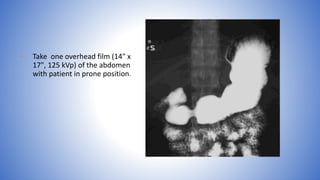

• Take one overhead film (14" x

17", 125 kVp) of the abdomen

with patient in prone position.

• Take oneoverhead film (14" x 17", 125 kVp) of the abdomen with patient in prone position.